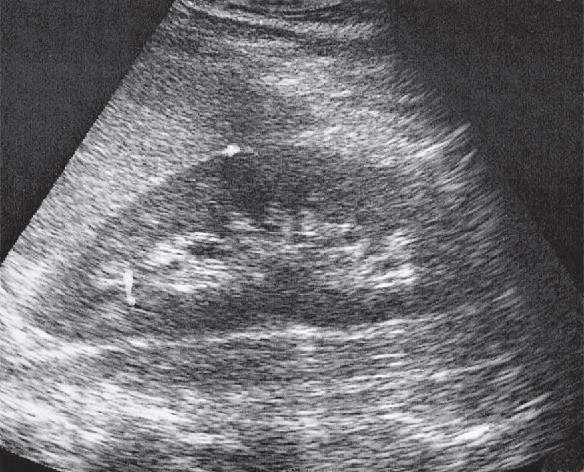

Które badanie zostało zarejestrowane na przedstawionym radiogramie?

Ilustracja do pytania 21

A. Jamy brzusznej wykonane poziomą wiązką promieniowania.

B. Płuc wykonane metodą Przybylskiego.

C. Układu moczowego z użyciem środka kontrastującego.

D. Dróg żółciowych metodą cholangiografii śródoperacyjnej.